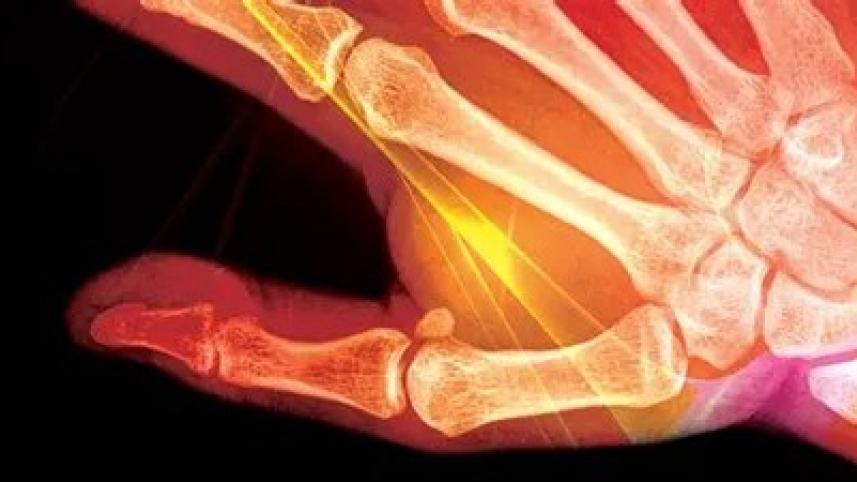

Few specific arthritic ailments often impact both men and women in our country, irrespective of age. Rheumatoid arthritis is often found in women — the patients experience pain in both small and large joints, which includes hands and feet.